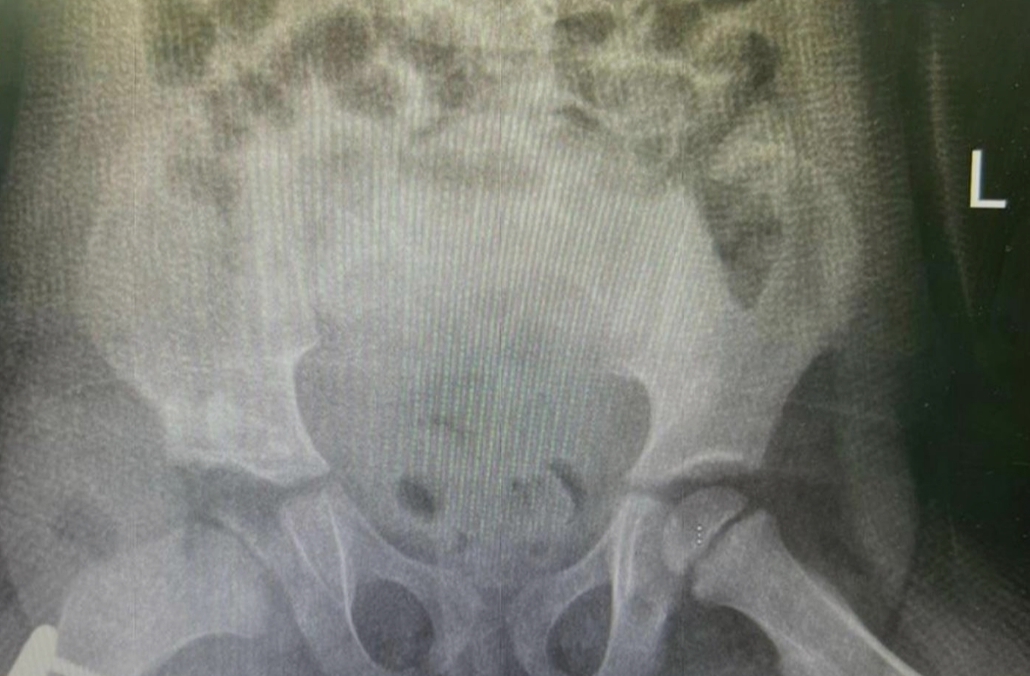

وأوضح قائد الفريق الطبي استشاري وبروفيسور عظام الأطفال الدكتور عمار العمران أن الطفلة البالغة من العمر 4 سنوات خضعت لعمل التقييم اللازم عبر الفحص السريري وعمل الأشعة، وقرر الفريق المعالج بعمل جراحة ترميم وتقويم للمفصل, مشيراً إلى أن الأشعة أوضحت بعد العملية التي استغرقت قرابة 4 ساعات نجاح العملية ورجوع مفصل الورك، وأن الفحوصات الإكلينيكية للمريضة كشفت تحسناً ملحوظاً في مستوى حركة مفصل الورك والأداء الوظيفي بدون ألم.